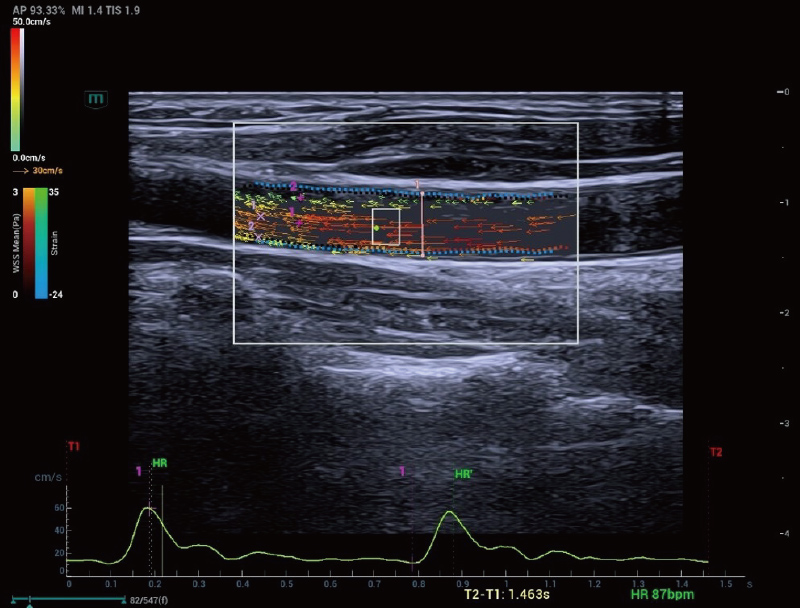

The Resona A20 introduces a new generation of vascular quantitative

analysis tools, featuring RF-data-based vascular pulse wave velocity

and wall shear stress analysis. These advancements aid in the

assessment of arterial vascular sclerosis.

Holo-PWV

V Flow and wall shear stress analysis

Carotid Artery | Holo-PWV